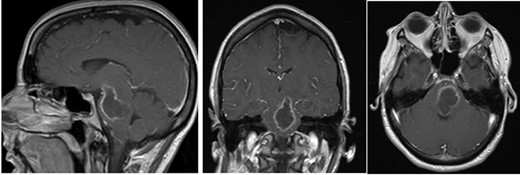

A 44-year-old female presented initially to an outside hospital with difficulty in speaking, right-sided facial droop and difficulty in walking. She also endorsed a 1-week history of intermittent headache. Magnetic resonance imaging (MRI) of brain demonstrated a ring-enhancing pontine lesion with surrounding vasogenic edema consistent with a brainstem abscess measuring 3.6 × 2.4 × 3.7 cm (Fig. 1a–c). There were no areas of ischemia. Pertinent history revealed no dental, cardiac or pulmonary source of infection. She had no history of intravenous drug use.

Pe-op axial, coronal and sagittal T1 post-contrast MRIs demonstrating rim-enhancing pontine abscess.